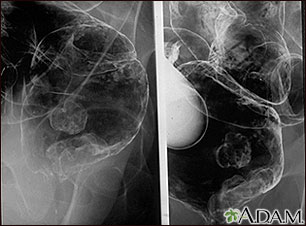

Rayos X de un cáncer rectal

Enema de bario en un paciente con cáncer de recto.